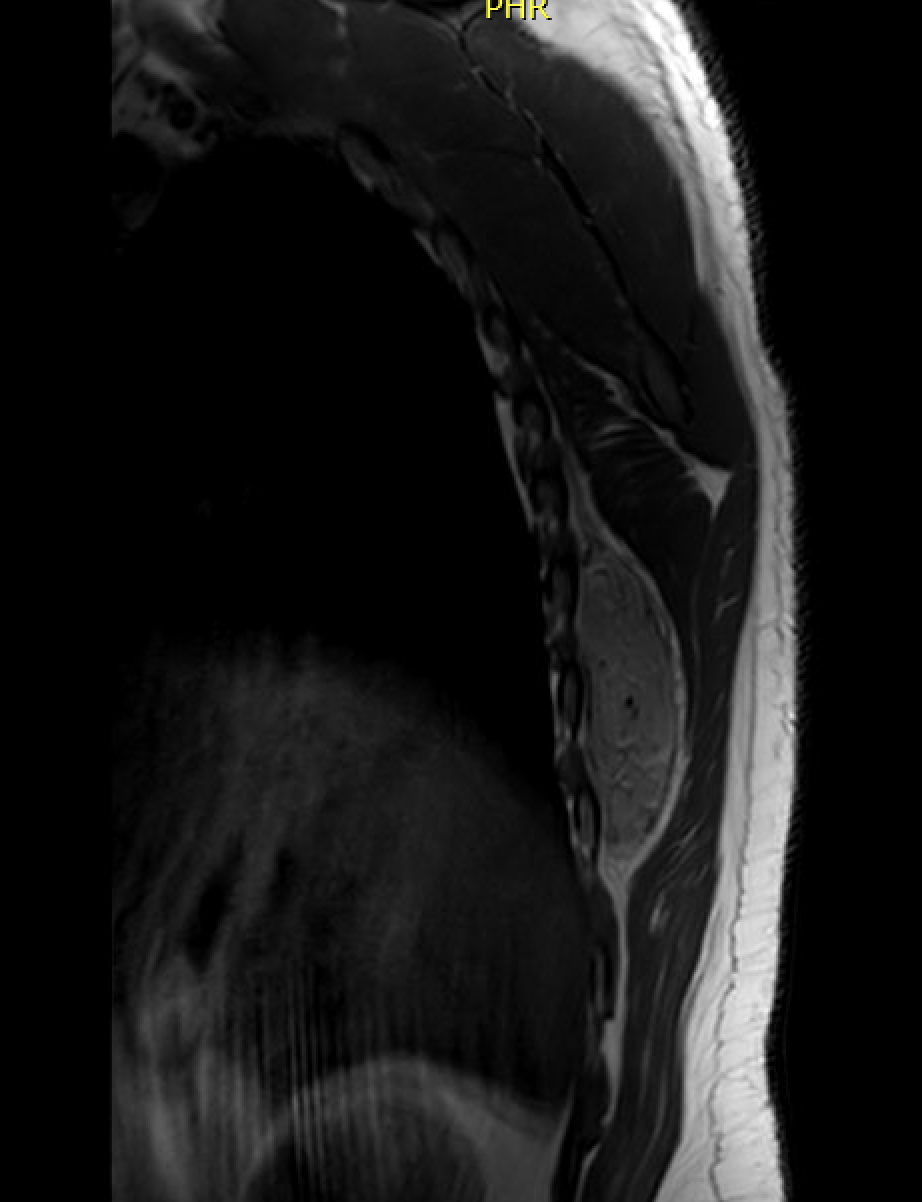

Grows beneath the rhomboid major and latissimus dorsi muscles adjacent to the inferior angle of the scapula

MRI

Semilunar, soft tissue mass abutting the rib cage posteriorly with well defined margins

Similar signal intensity to muscle